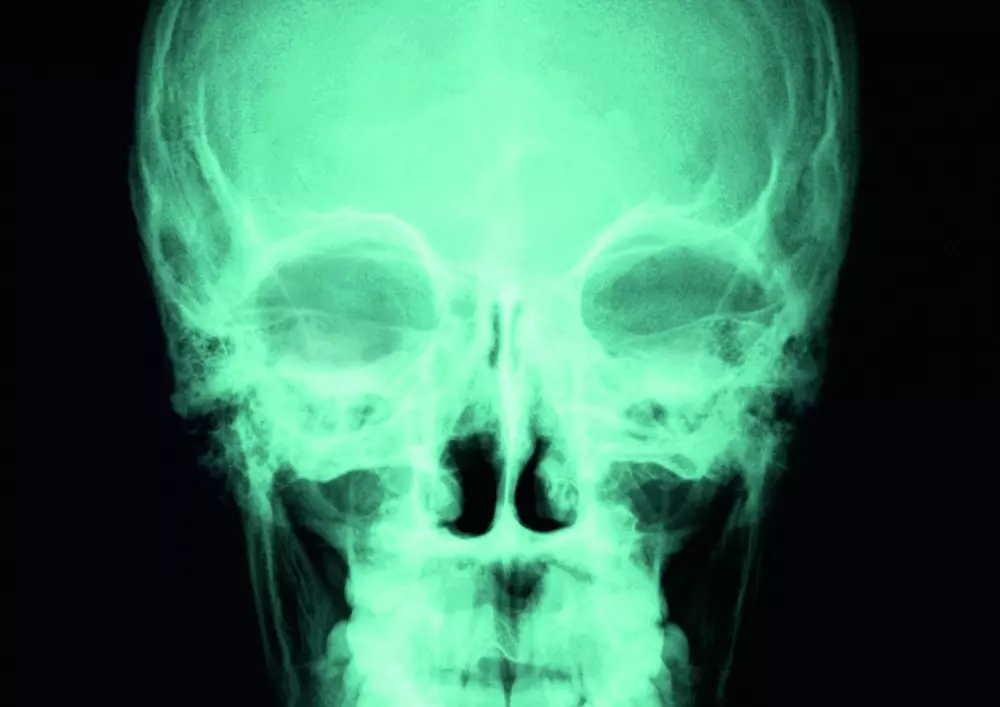

Rehabilitacja w urazach czaszkowo-mózgowych

Polecamy także lekturę artykułu pt. „Rehabilitacja w urazach czaszkowo-mózgowych”. Urazy tego typu zwykle nie niosą za sobą poważnych konsekwencji, jednak niewielka część poszkodowanych musi być hospitalizowana, a 9 na 100 tys. osób umiera wskutek obrażeń. Ponadto część osób, która przeżyła uraz czaszkowo-mózgowy będzie do końca życia skazana na niepełnosprawność i wymagała stałej rehabilitacji.